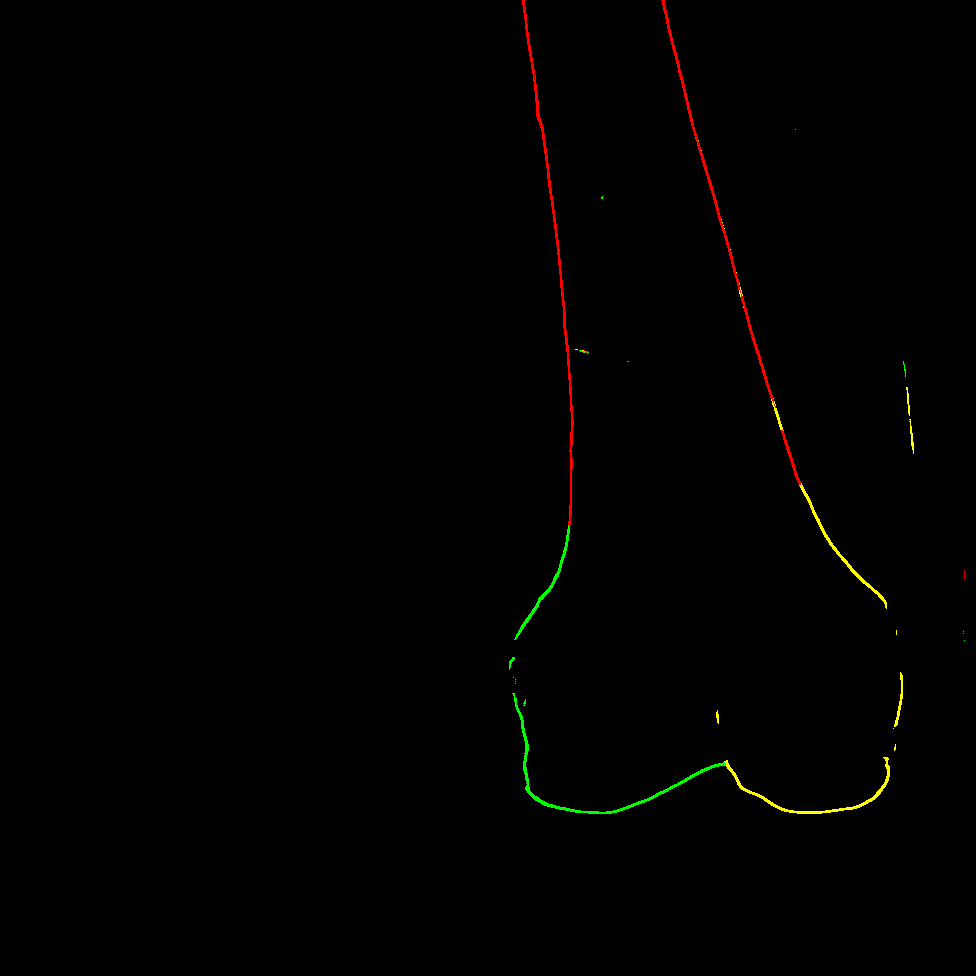

The key idea behind our contour-based ICP registration method is to achieve accurate 2D/3D matches using component-level contours instead of object-level ones. This raises the question of how to define component classes based on the anatomy of the femur. Although X-rays are transparent, for the sake of clarity, we assume the femur to be an opaque object for now and focus specifically on its occluding contours, which appear in the X-ray as sudden changes in tissue density. We recall that for an occluding contour to form, the shape must be locally convex in the viewing direction. In other words, at the point where the occluding contour is observed, the surface of the object must curve outward toward the observer.

Based on this definition, we propose dividing the femur into three convex substructures, each associated with a contour category, that are convex with respect to an observer (the C-arm) rotating around the diaphysis’s main axis: diaphysis, the medial condyle and the lateral condyle (shown Figure 1) of class indices in the following.

In this section we want to give a visual explanation of our contour matching. Unlike registration methods relying on object-level contours (see Figure 8, left), we propose extracting component-level contours, specifically those of anatomical substructures (see Figure 8, right).